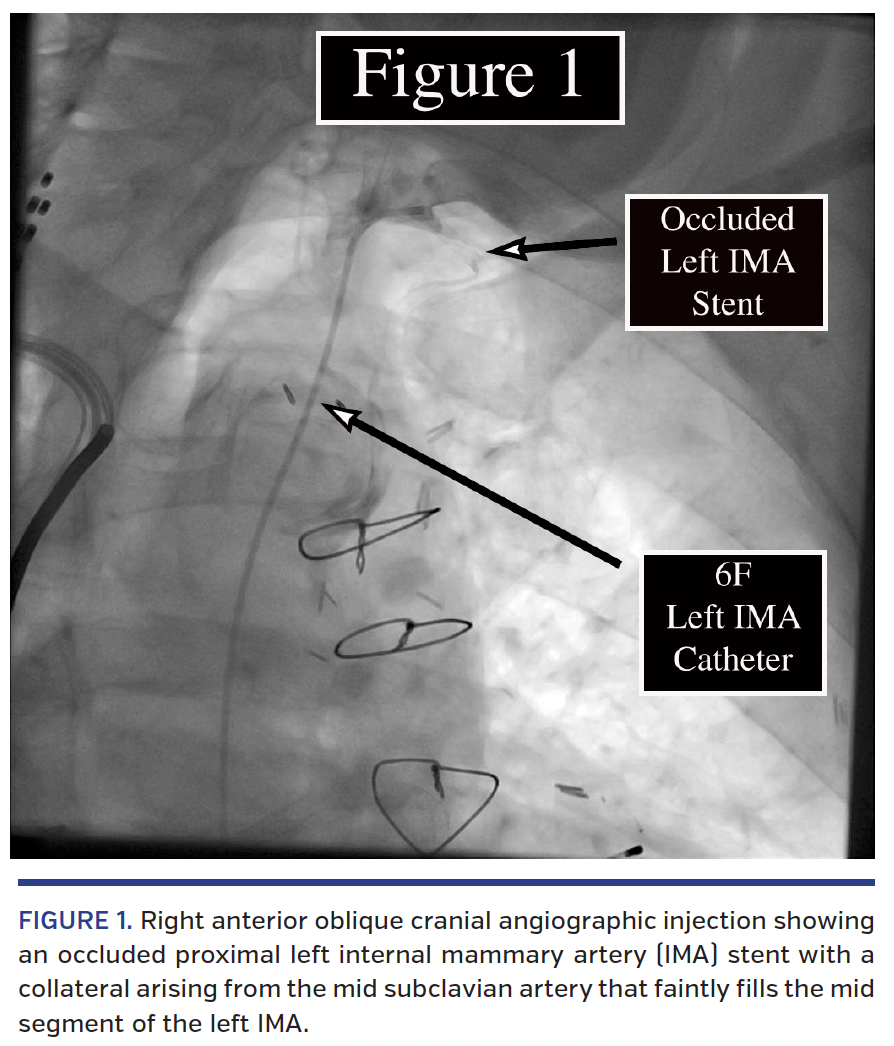

An 84-year-old man had a history of two prior coronary artery bypass graft operations, multiple percutaneous coronary interventions, and left ventricular systolic dysfunction. He presented with recurrent angina, Canadian Cardiovascular Society angina class III. Coronary angiography revealed severe three-vessel coronary disease and bypass graft angiography revealed a totally occluded stent in the proximal left internal mammary artery (LIMA) (Figure 1). As such, percutaneous LIMA intervention was planned. A 180 cm Kinetix wire (Boston Scientific) was advanced into the occluded LIMA via a 6 Fr LIMA guide catheter. The tip of the wire became entrapped in the stented segment of the occluded vessel. Further manipulation resulted in wire fracture. The body of the wire was removed while approximately 20 centimeters of the soft tip remained in the patient, with half in the LIMA and the other half free in the left subclavian artery (Figure 2). Traditional retrieval techniques were unsuccessful. A novel retrieval technique was attempted. A Balance Middleweight universal coronary wire (Abbott Vascular) was advanced anterior and distal to the fractured wire. The guide catheter was torqued posteriorly, and an Amplatz GooseNeck Microsnare (Covidien) was advanced into the mid subclavian artery also distal to the fractured wire. The shaft of the Balance Middleweight wire, rather than the soft tip, was snared distal to the fractured wire. As the Microsnare and snared Balance Middleweight wire were pulled back, the Kinetix wire that had been positioned between the two devices was securely trapped and successfully removed from the patient (Video 1). Although fractured coronary wires are a rare occurrence, failures to retrieve them successfully put patients at undue risk.1 This technique can be used when traditional retrieval with a Microsnare system is unsuccessful.